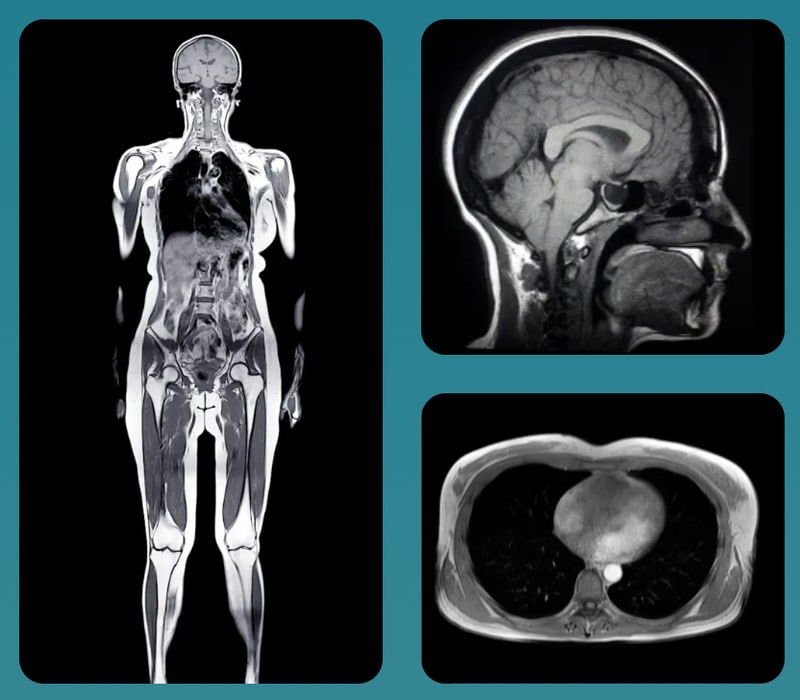

Prenuvo operates a growing network of clinics specializing in full-body preventive MRI scans designed to catch medical conditions before they become symptomatic. The technology screens for early-stage diseases including Alzheimer's, aneurysms, spine degeneration, and certain cancers. The startup charges $2,499 for a comprehensive full-body scan or $999 for a torso-only option, with patients covering costs through health savings accounts or out-of-pocket payment since these elective scans fall outside traditional insurance coverage. The company has already completed roughly 150,000 scans across its current network of 24 clinics.

The approach rests on straightforward logic: detecting disease at its earliest stages gives patients more options and better outcomes. Prenuvo reports that between 2.5 and 5 percent of patients discover previously unknown life-threatening conditions, while nearly half learn of conditions requiring ongoing monitoring. The scans use advanced MRI technology to examine soft tissues, organs, and vascular systems in meticulous detail. With plans to expand to 41 total clinics, Prenuvo is positioning preventive imaging as a proactive health tool for those willing to invest in early detection outside the traditional healthcare system.

Image Credit: Prenuvo